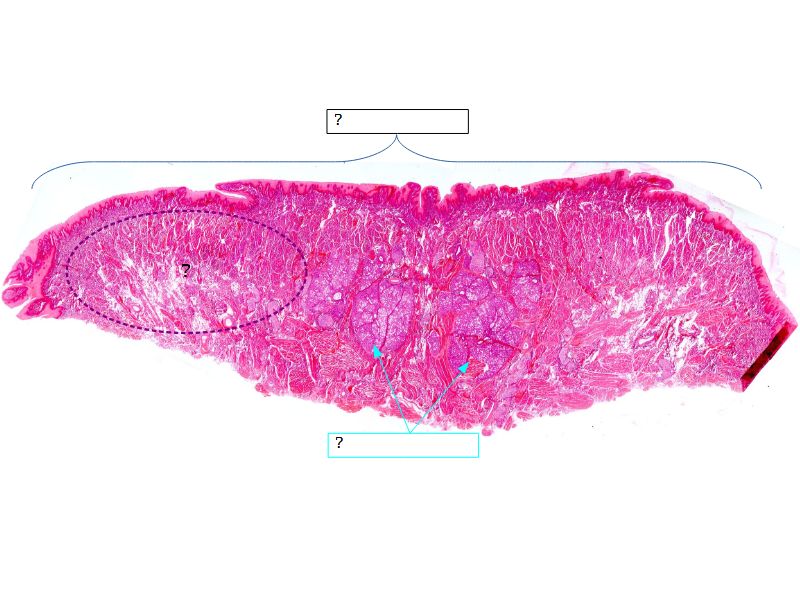

Fill in all the missing labels, and assess as you move through the slides. Answers on the down slide. It is important to do this using pen and paper, and not just glance through the images.